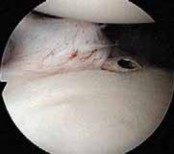

The surgical approach begins with the establishment of a standard posterior viewing portal, placed approximately 2 cm inferior and 1 cm medial to the posterolateral corner of the acromion. Upon entering the joint, a meticulous diagnostic sweep is performed. The surgeon must systematically evaluate the biceps anchor, the superior labrum, the articular surfaces of the humerus and glenoid, the rotator cuff footprint, and the entire capsulolabral complex. Particular attention is directed to the anteroinferior quadrant to confirm the presence of a Bankart or ALPSA lesion. The size and depth of any Hill-Sachs lesion are evaluated dynamically by taking the arm through a range of motion to assess for "engagement" over the anterior glenoid track.

The foundation of a successful arthroscopic stabilization is the meticulous mobilization of the capsulolabral complex. In chronic cases, the torn labrum and IGHL frequently heal in a medially displaced position along the anterior glenoid neck (the ALPSA lesion). Using a combination of arthroscopic elevators, rasps, and electrocautery, the surgeon must aggressively liberate this tissue from the scapular neck. The release must extend inferiorly to the 6 o'clock position to adequately mobilize the inferior capsule. Once the tissue is freed and can be easily reduced to the articular margin, the anterior glenoid neck is lightly decorticated using a motorized burr or rasp. This critical step removes fibrous tissue and exposes bleeding cancellous bone, creating an optimal biological environment for robust soft-tissue healing.